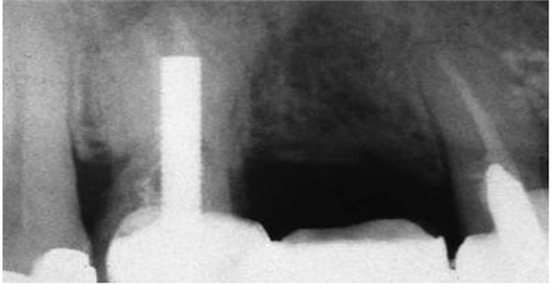

圖2:上頜第一前磨牙的根尖片,過長的平行壁樁修復(fù),根尖部的牙膠量少于理想的5mm的根尖封閉

牙髓治療后的牙齒經(jīng)過樁道的預(yù)備,根尖部的牙膠是抵抗根尖周區(qū)域細菌傳播的屏障。許多研究結(jié)果都已經(jīng)證實當根尖部的牙膠長度僅僅是2mm到3mm時,根管內(nèi)存在嚴重的滲漏;根尖部牙膠量為4mm到5mm能保證充足的根尖封閉。盡管多數(shù)研究結(jié)果都表明4mm的根尖牙膠量能提供充足的根尖封閉,但是樁道預(yù)備時要精確地達到4mm是非常困難的,根尖片拍攝角度的差異可能會導(dǎo)致根尖部保留的牙膠少于4mm。因此在根尖片上,根尖部牙膠5mm比4mm更為對根尖封閉安全有效。